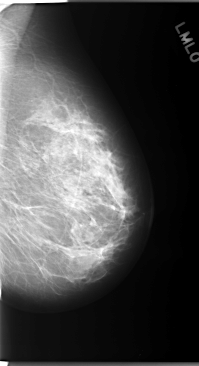

C_0101_1.LEFT_MLO

LEFT_MLO LINES 5856 PIXELS_PER_LINE 3176 BITS_PER_PIXEL 12 RESOLUTION 50 NON_OVERLAY